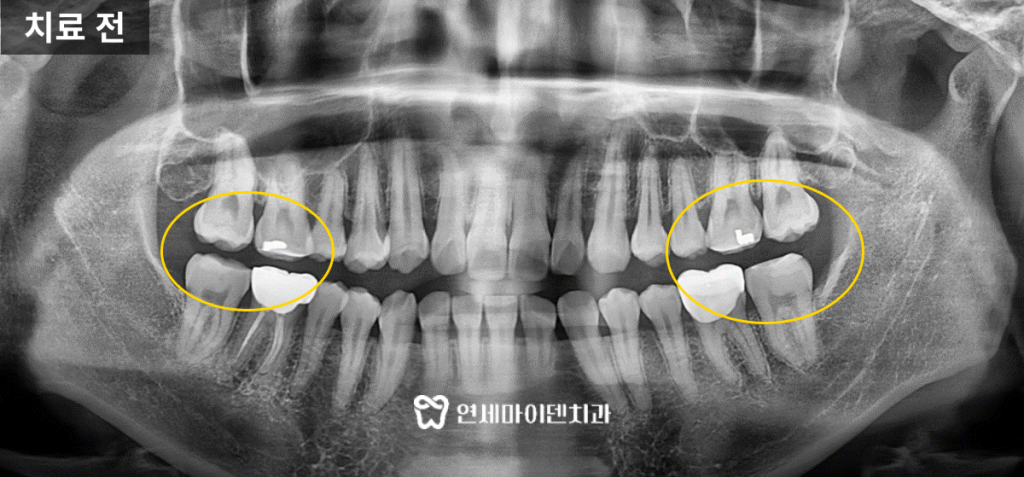

내원 당시, 환자분은 어금니에 레진을 올려 교합면을 높인 상태였습니다.

하얀 레진이 군데군데 올라가 있었고,

이로 인해 작은 어금니와 앞니가 맞물리지 않는 ‘교합 이탈’ 상태였습니다.

환자분의 치아를 전체적으로 살펴보면,

어금니 쪽에 하얗게 올려져있는 레진이 보입니다.

특히, 끝에서 두 번째의 큰 어금니들의 크라운이 높게 만들어져 있어서

송곳니나 작은 어금니들 모두 교합이 안되고 뜨는 상태였습니다.

또, 이전 교정 치료 중 위쪽 앞니의 치간 삭제를 많이 해서

아래 앞니와 사이즈가 비슷할 정도로 치아가 갈려있는 상태였습니다.